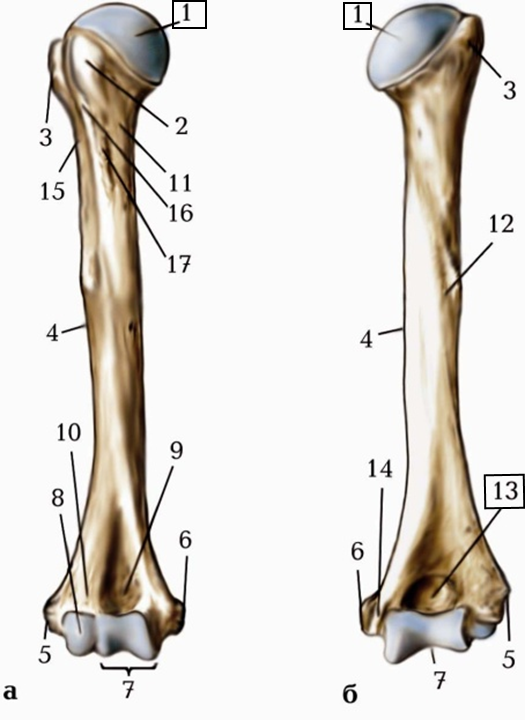

ЯК НАЗИВАЄТЬСЯ ЦЯ КІСТКА?

варіанти відповідей

FIBULA

TIBIA

HUMERUS

RADIUS

ULNA

CLAVICULA

STERNUM

FEMUR

Запитання 4

ПІСЛЯ АВТОМОБІЛЬНОЇ АВАРІЇ НА РЕНТГЕНОГРАМІ ВИЯВЛЕНО ПЕРЕЛОМ КІСТКИ В ДІЛЯНЦІ ХІРУРГІЧНОЇ ШИЙКИ. ЯКА КІСТКА МАЄ ТАКУ ШИЙКУ?

ПЕРЕЛОМ ЯКОЇ КІСТКИ І ЯКОЇ ЇЇ ЧАСТИНИ ВИ БАЧИТЕ НА РИСУНКУ?

ДИСТАЛЬНОГО ДІАФІЗА

ПРОКСИМАЛЬНОГО ЕПІФІЗА

ДИСТАЛЬНОГО ЕПІФІЗА

ДІАФІЗА

МЕТАФІЗА

ЯКОЮ ЦИФРОЮ ПОЗНАЧЕНИЙ ВЕЛИКИЙ ВЕРТЛЮГ? (В АКУШЕРСТВІ ВИМІРЮЮТЬ ВЕРТЛЮГОВУ ДИСТАНЦІЮ).

2

6

7

3

4

11

12

ЩО ІЗ ПЕРЕРАХОВАНОГО МАЄ FEMUR НА ПРОКСИМАЛЬНОМУ ЕПІФІЗІ?

2 ВИРОСТКИ

2 НАДВИРОСТКИ

ВЕЛИКИЙ ВЕРТЛЮГ

МАЛИЙ ВЕРТЛЮГ

ТУПИЙ ШИЙКО-ДІАФІЗАРНИЙ КУТ